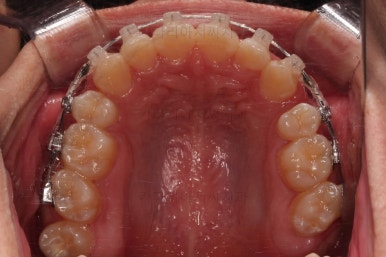

순차적으로 장치를 붙여가며 치아를 가지런하게 합니다.

가지런하게 하는 단계를 거친 뒤,당기기 과정에 들어가는데요.

이 과정에서 입이 들어가는 양, 중앙선, 기울기, 앞니 각도 등등 많은 것을 신경써서 당기기를 해주는데요.

이 때 필요한 것이 미니스크류 입니다.

예전과는 다르게 미니스크류를 이용해서 좀 더 정교하고 고난이도의 치료가 가능해지게 된거죠.